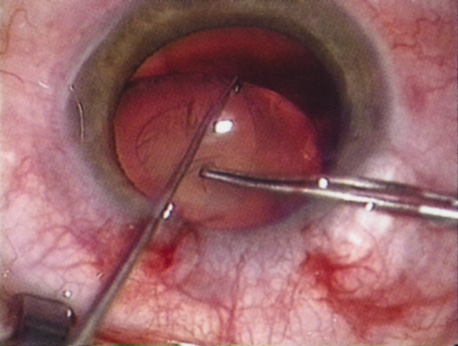

HYDRODISSECTION Hydrodissection can be performed after the surgeon has successfully completed capsulorrhexis.97 If the capsulorrhexis is not intact, fluid forced around the interior of the capsule may cause the bag to splay open. With capsulorrhexis, hydrodissection is a safe and extremely useful maneuver. Hydrodissection can be thought of as two maneuvers: hydrodelineation and cortical cleaving hydrodissection. By placing a 27-gauge cannula on a syringe filled with balanced saline solution (BSS), the surgeon can direct fluid beneath the residual anterior capsular rim to create a cleavage plane. Depending on the direction the fluid wave takes, different lamellae of the cataract will be separated. Hydrodelineation is the term used when the cleavage plane separates the adult nucleus from the fetal nucleus or the adult nucleus from the more peripheral epinucleus. Hydrodelineation often results in the characteristic golden ring sign (Fig. 11). Cortical cleavage occurs when the cortex is separated from the capsular bag (Fig. 12). Finding the cortical cleavage plane may be facilitated by gently lifting the capsular margin away from the cortex with the BSS cannula before injecting. Several small bursts of fluid allow the surgeon to monitor progress of the fluid wave. When dealing with a soft nucleus, the authors strive to perform true cortical cleaving hydrodissection. For a hard nucleus, hydrodelineation allows manipulation of less of the nuclear bulk, although the remaining epinuclear shell must be addressed in an additional step. Hydrodelineation is particularly useful if the nucleus is not freely mobile after cortical cleaving hydrodissection.